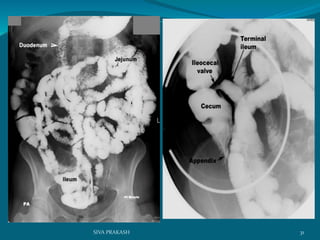

BA Meal follow through:

28SIVA PRAKASH

29SIVA PRAKASH

The pattern of the mucosal lining of the first part of the duodenum is different

from the other parts. longitudinal pattern of the mucosa of the first part of the

duodenum forming what is known as the duodenal cap This pattern is very

similar to that of thepylorus of the stomach This pattern changes to a

more flecked appearence in the distal duodenum

30SIVA PRAKASH

31SIVA PRAKASH